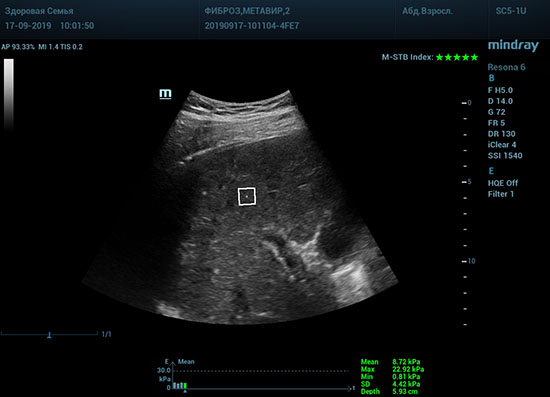

Определение плотности печени. Не ошибся ли оператор при измерении эластических свойств печени? Для оценки критериев качества предусмотрен индекс MBT, который покажет насколько «твердой» была рука оператора и двигалась ли печень. При MBT 5* рука тверда и показатели достоверны. Для оценки качества результатов используется IQR индекс, отображающий колебания показателей в точке измерения при расчете медианы. Показатели при IQR <30% считаются приемлемыми. Техника сканирования через межреберные промежутки требует размещение окна интереса на несколько сантиметром ниже капсулы, для исключения эффекта реверберации. Установка ROI на паренхиму без захвата сосудов, для исключения погрешностей измерения.

Стадия фиброза определяется по системе METAVIR Staging, построенной на данных биопсии и сопоставлении с данными эластографии. Своевременная диагностика фиброза, и начало его лечения, залог благоприятного исхода заболевания.